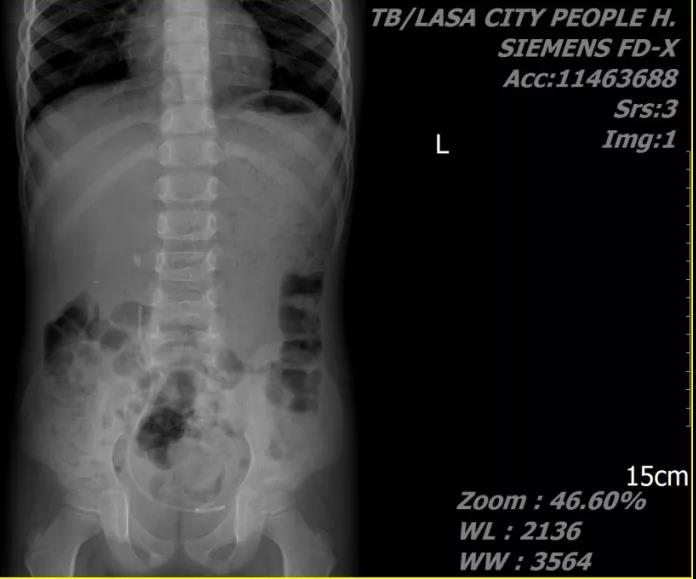

患儿,男,8月龄,主因“排尿困难伴哭闹1日”就诊。术前诊断:双肾结石;予以右侧mPCNL。